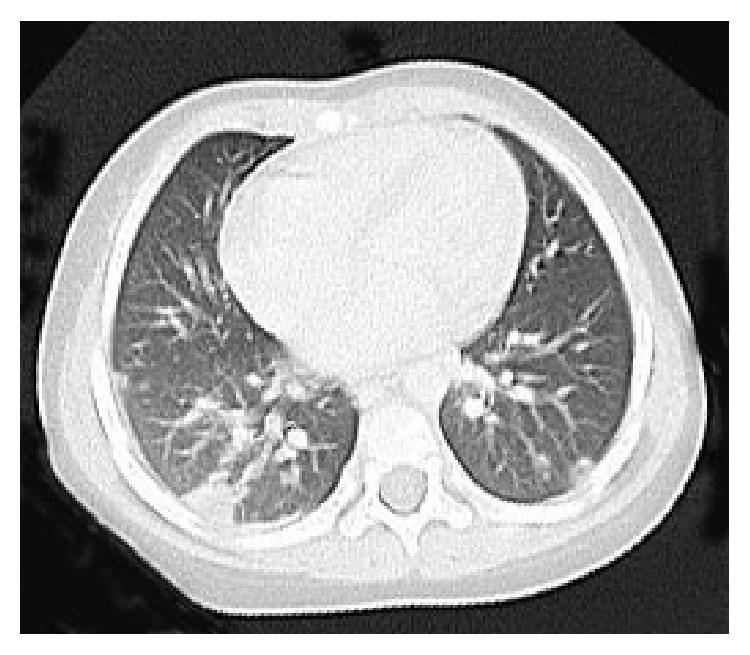

Pediatric invasive community-acquired methicillin-resistant Staphylococcus aureus (CA-MRSA) infection is very serious and occasionally fatal. This infectious disease is still a relatively rare and unfamiliar infectious disease in Japan. We report a positive outcome in a 23-month-old Japanese girl with meningitis, osteomyelitis, fasciitis, necrotizing pneumonia, urinary tract infection, and bacteremia due to CA-MRSA treated with linezolid. PCR testing of the CA-MRSA strain was positive for PVL and staphylococcal enterotoxin b and negative for ACME. SCC mec was type IVa. This case underscores the selection of effective combinations of antimicrobial agents for its treatment. We need to be aware of invasive CA-MRSA infection, which rapidly progresses with a serious clinical course, because the incidence of the disease may be increasing in Japan.

儿童侵袭性社区获得性耐甲氧西林金黄色葡萄球菌(CA-MRSA)感染非常严重,偶尔会致命。这种传染病在日本仍然是一种相对罕见且不为人熟悉的传染病。我们报告了一名23个月大的日本女孩因CA-MRSA感染导致脑膜炎、骨髓炎、筋膜炎、坏死性肺炎、尿路感染和菌血症,使用利奈唑胺治疗后取得了良好疗效。对该CA-MRSA菌株进行PCR检测,结果显示Panton-Valentine杀白细胞素(PVL)和葡萄球菌肠毒素b呈阳性,ACME呈阴性。葡萄球菌染色体盒式Mec(SCC mec)为IVa型。该病例强调了选择有效的抗菌药物联合治疗的重要性。我们需要警惕侵袭性CA-MRSA感染,其临床病程严重且进展迅速,因为在日本这种疾病的发病率可能正在上升。